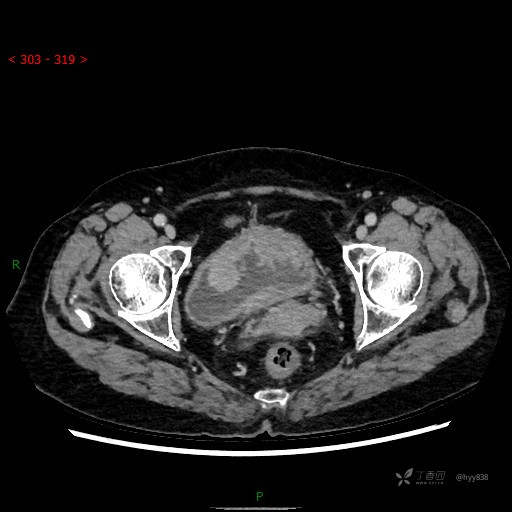

膀胱少见肿瘤,欢迎挑战---结果公布~

华夏览雄 达人已点赞患者性别:女

患者年龄:73岁

主诉:肉眼血尿3周

简要病史:患者诉3周前无明显诱因开始出现肉眼血尿,发作时尿液呈鲜红色,为全程血尿,无明显血凝块;伴小腹胀痛,无尿频、尿急、尿痛;无寒战、发热;无恶心、呕吐,就诊于当地医院行输液治疗后,出现不规则血凝块,进一步完善相关检查提示膀胱占位,活检提示膀胱炎性改变,现患者为进一步治疗,遂来我院,门诊以“膀胱肿物”为主诉入院。 起病以来,患者精神、饮食、睡眠稍差,大便如常,小便如上述,近期体力、重无明显变化

临床诊断:膀胱肿瘤

膀胱CT平扫(2022.10.20)

增强(2022.11.1)